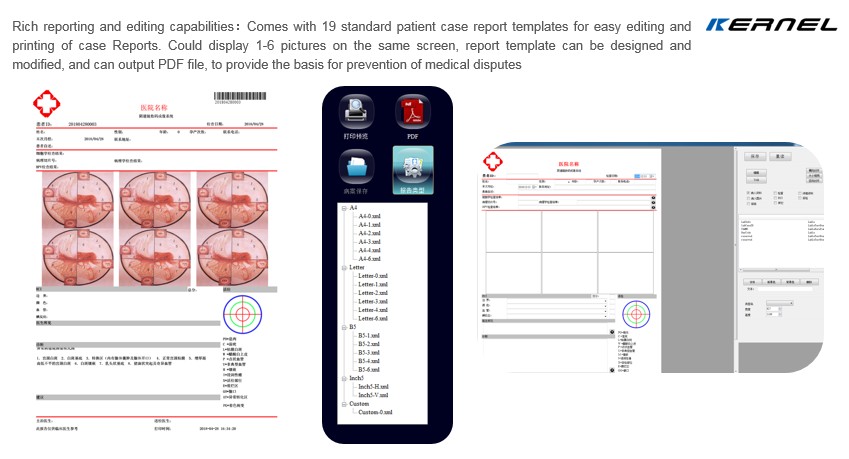

About software

All of our colposcope come with Free Multifunctional software

>>>>8 operating languages:

Chinese,English,Spanish,Russian,Turkish,Italian,France,Vietnamese

>>>>Capture Images,Take Videos,Acetic Acid test timing ,Case report,175 Clinical disgnostic data bases comparison